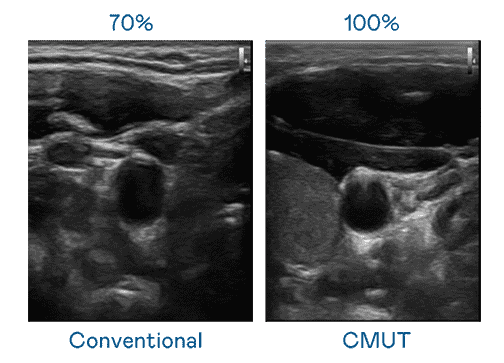

CMUT 技术是一种用电容式微机电元件来产生超音波讯号的技术。。。与传统 PZT 压电式技术相比,,,CMUT 频宽增加 30%,,,更宽频的超音波讯号让影像解析度大幅提升,,是实现高影像品质医疗超音波扫描、、促进精准医疗发展的关键技术。。

超音波影像的解析度高低,,首先取决于探头能发出的讯号频宽。。人生就是博 CMUT 可提供高清晰的超音波讯号,,提供高频宽、、、、高灵敏度、、、影像纹理细节更高的超音波影像,,协助医护人员缩短影像判读时间及利用精准的医疗影像进行诊断。。。。